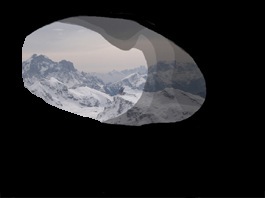

Le prime alterazioni visive, evidenziabili solo con gli esami strumentali, compaiono quando l’atrofia ha già interessato circa il 30% delle fibre del nervo ottico. Si tratta di aree localizzate (di solito alla periferia del campo visivo) in cui la sensibilità della funzione visiva è ridotta rispetto alla norma o scomparsa (vedi foto sotto). In tale fase il paziente non avverte alcuna difficoltà visiva, in quanto la zona centrale del campo visivo, utilizzata ad esempio per leggere, scrivere o guidare, è integra.

A sinistra: campo visivo integro (occhio sano). A destra: difetto della parte inferiore del campo visivo (glaucoma)

Se il danno del nervo ottico progredisce, le alterazioni del campo visivo progressivamente si estendono e giungono ad interessare anche l‘area centrale. E’ a questo punto che spesso il paziente si accorge delle difficoltà visive, che possono consistere sia nella mancata percezione di oggetti posti a lato sia nell’impossibilità di leggere.

Nelle fasi terminali può residuare solo un’isola centrale di visione, nel qual caso si ha la sensazione di vedere come attraverso un tubo (“visione tubulare”, vedi foto a destra), finché non scompare anche quest’ultima.